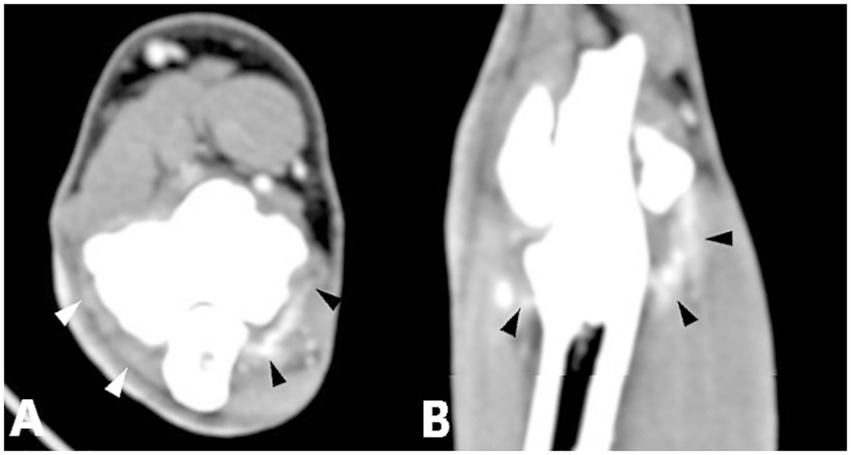

The primary diseases described below generally included additional periarticular osteophytes, which is not listed separately. Periarticular osteophytes were analyzed separately. There was a significant correlation between MCPD (n = 196), UAP (n = 3), and enhancement of the joint capsule compared with the control group. An epicondylar spur (n = 8) showed a significant correlation with flexor muscle enhancement compared with the control group (Figure 3). No significant difference from the control group was observed for other single primary diseases and no statistical significance could be calculated where enhancement was absent or case numbers were insufficient (Table 7).

Figure 3. Computed tomography slices of elbow joints with a single primary disease showing significant correlation with contrast enhancement of the joint capsule or flexor muscles. (A,B) Left elbow joint with MCPD showing contrast enhancement of the joint capsule (black arrowheads). (C,D) Right elbow joint with UAP showing contrast enhancement of the joint capsule (black arrowheads). (E,F) Left elbow joint with an epicondylar spur showing contrast enhancement of the flexor muscles (black circle).